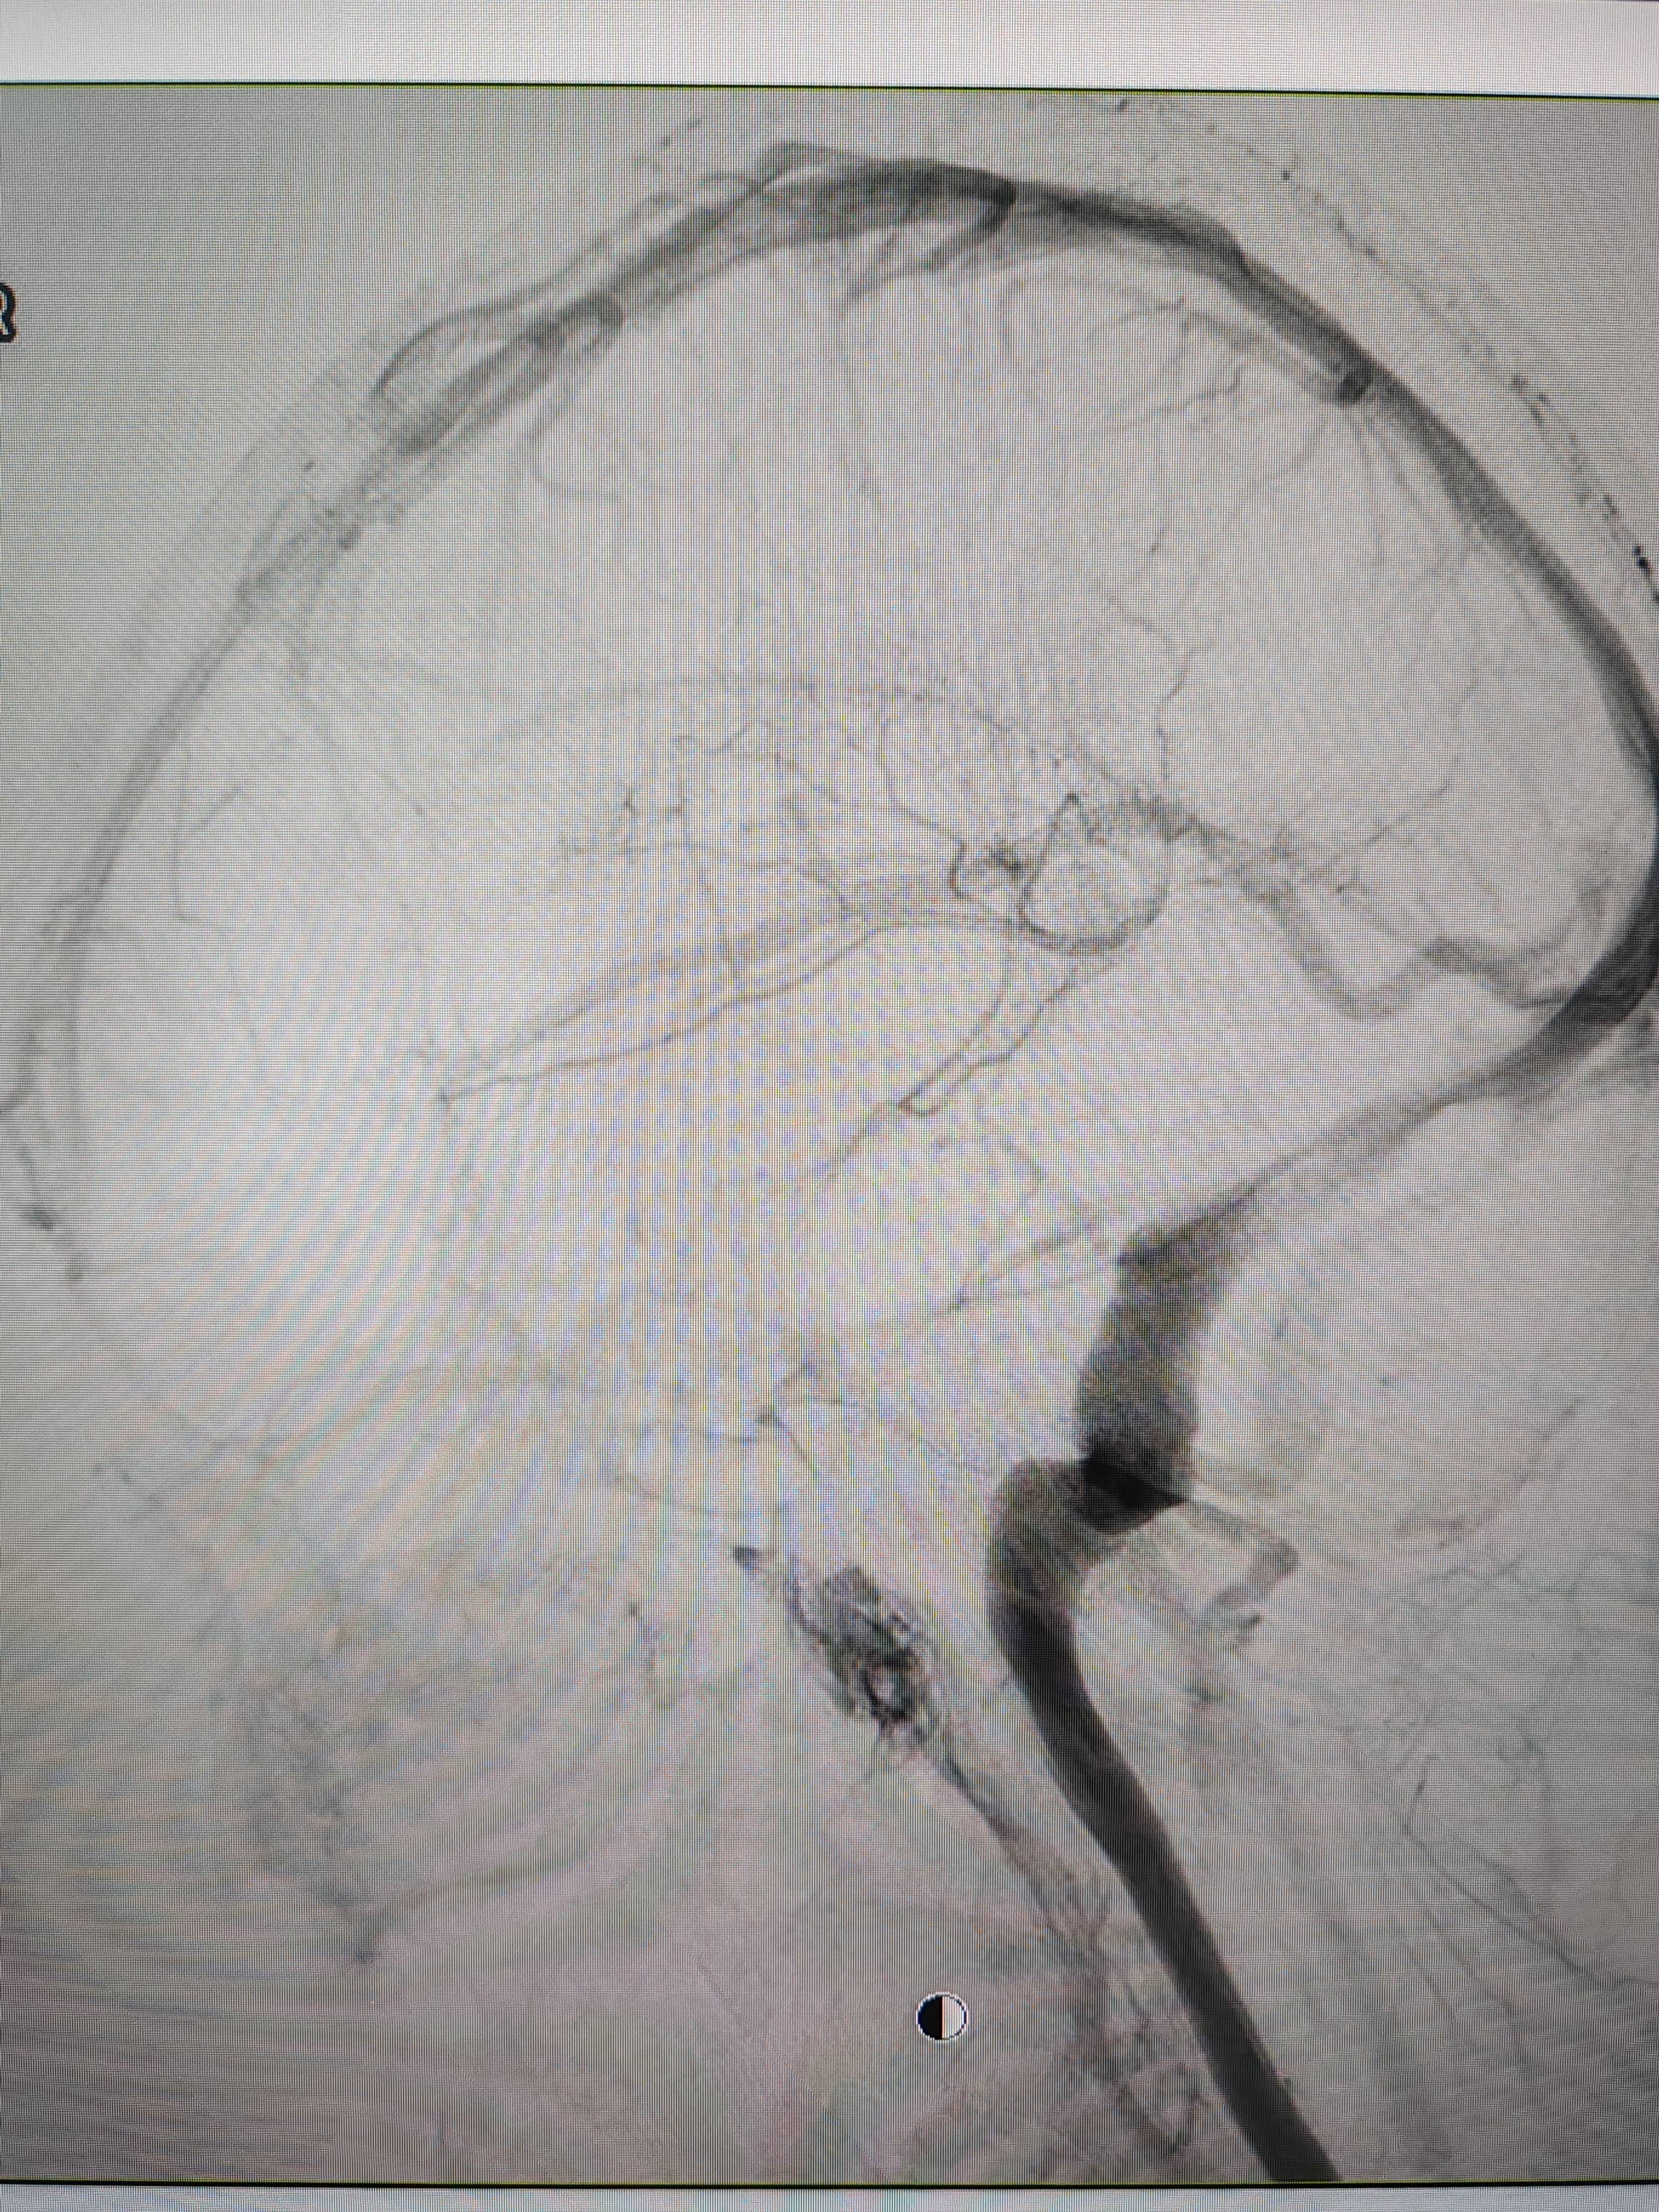

患者造影图像显示,其耳侧静脉窦狭窄。 南方+ 欧阳少伟 拍摄

李宝民举例说,通过查体、CT、造影等影像技术的检查,患者赵女士是由于静脉窦狭窄,导致缓慢的静脉血流也出现“湍流”现象,其拐弯、打漩涡、回流产生的声响,又顺着骨传导,传至耳蜗处,进而让患者出现搏动性耳鸣的症状。